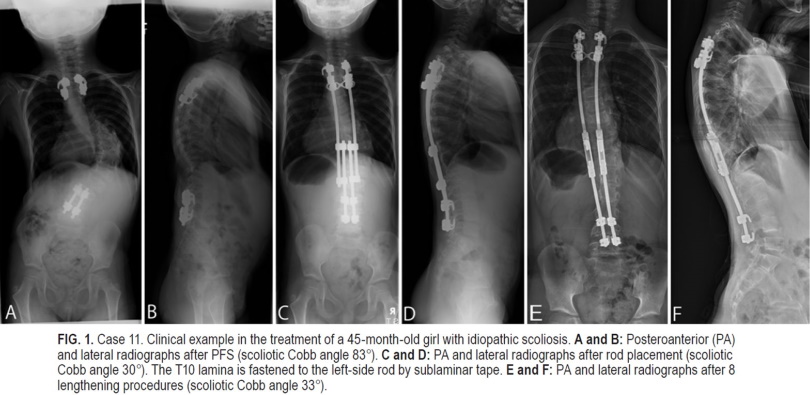

El objetivo de este estudio fue mostrar los resultados quirúrgicos de la cirugía de varilla en crecimiento (GR) con cirugía previa de base (PFS) y cinta sublaminar en una vértebra del ápice.

Una técnica de doble GR con cirugía de base previa (SLP) y cinta adhesiva sublaminar mostró una corrección efectiva de las curvas escolióticas y una tasa de complicaciones menor que los informes anteriores cuando se utilizó una técnica de doble GR convencional.